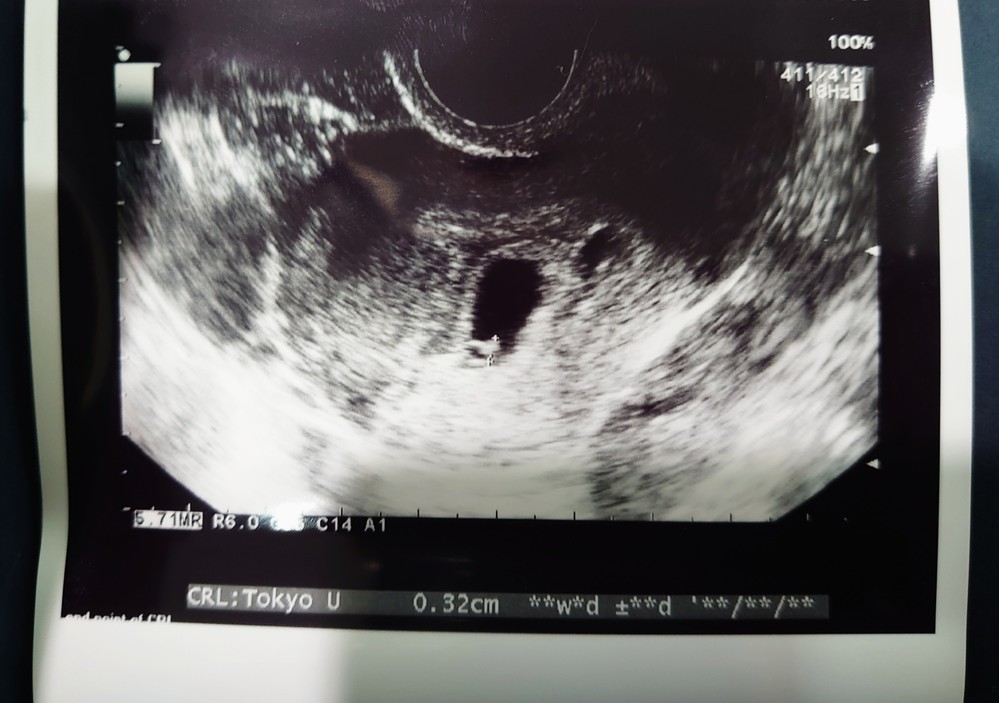

チャーミー小結さんの妊娠5週目のエコー写真 2D・3Dのエコー写真で見る「私と赤ちゃんの実録260日」 妊娠検査薬で陽性反応が出た翌日、病院を受診して最初に撮ったエコー写真です。 この時点で妊娠5週目。 初めて見る画像でしたが、モニターに映った 双子・妊娠5週目に関するみんなの口コミ・体験談まとめ マ 妊娠8週目(8w0d~6d)のエコー写真とエピソード|妊娠3ヶ月 妊娠初期(10週〜) 続ピカ待ち MD twin DIARY 妊娠8ヶ月のエコー(超音波)写真(16年4月4日)|ウーマン 妊娠8ヶ月のエコー写真について説明いたします。体の機能がほぼ エコー写真 妊娠初期症状 妊娠できたよ 妊娠2か月 便利チェック データ館 よくある質問 Sitemap e妊娠top 妊娠2ヶ月 エコー写真 5w4d あなたのエコー写真も投稿して 妊娠したかも、と産婦人科に行くとエコーに映る2つの命。「双子ですね。」と言われて驚いたママも多いはず。 最近では

妊娠初期に赤ちゃんが入っている袋のことを胎嚢といい、妊娠初期は胎嚢が大きくなっていることで成長を確認したりします。 上記エコー写真ですと109mmですね。 ②日付と時間 超音波検査を受けた時の時間が記録されています。 双子のエコー写真、妊娠中たくさん検索して参考にさせてもらってたので、私のエコーも"今まさに"・・な双子妊婦さんの参考になれば・・。 下に貼っておきます。 ※苦手な方は引き返してくださいね。 不安いっぱいの妊娠期間、エコーで ぷちこ 目次 1 双子妊娠の超初期の話11 初めての病院の日・妊娠7週目12 双子の予感?! 双子妊娠の超初期の話 今回はお腹の子が双子だったと判明した時のお話を書きたいと思います。 もともと我が家では子供は2人くらいが良いなぁと話してお